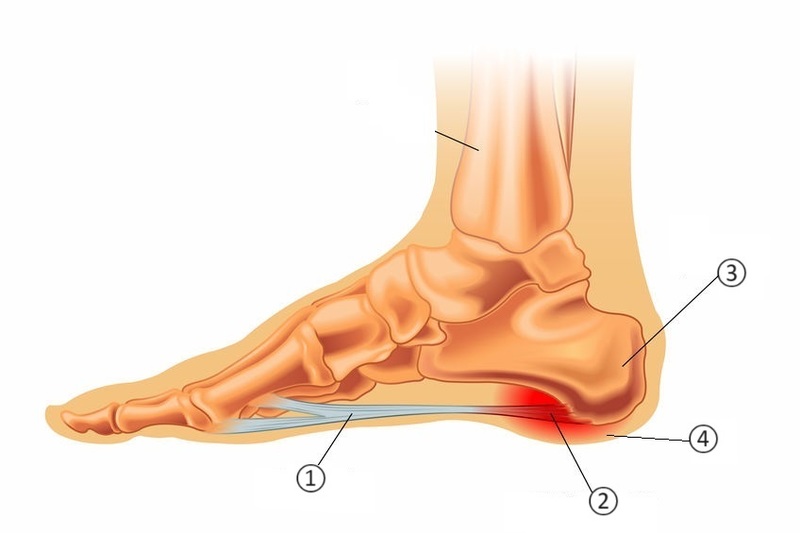

足底腱膜炎

①足底腱膜(実質部)

足の指の付け根から踵(かかと)に伸びる腱の膜状な組織

②足底腱膜(踵骨付着部)

足底腱膜と踵を結ぶ部分

③踵骨

かかとの骨

④踵骨下脂肪体

踵に下に存在する柔らかい組織

①足底腱膜は、足が体重を支えている時に張力を受ける組織として機能することで足のアーチの支持に関係しています。また足趾(足のゆび)を反らすと足底腱膜が緊張するため、歩行時の推進力としても機能します。つまり体重がかかった際の衝撃吸収の役目や歩行時に機能が発揮されているため、スポーツにおける長時間走行や仕事における長時間立位などで②付着部が炎症になります。

④踵骨下脂肪体はかかとの骨の下にある脂肪組織で衝撃吸収のクッションの役割をしています。足底腱膜やアキレス腱と連結しており、それらの硬さによって緊張されると、正常な圧縮反応が働かず、衝撃吸収ができなくなります。

上記の構造で衝撃吸収がうまく果たされないと、③踵骨自体が炎症し痛みを生じる病態にまで至ることもあります。